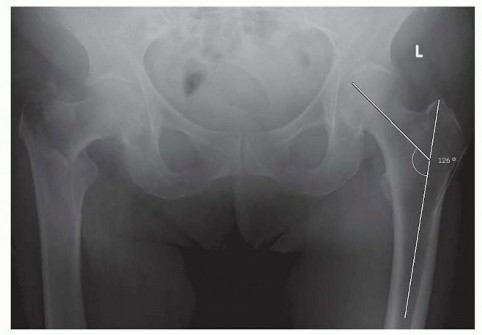

### FIG 2 • AO/OTA classification of proximal femur fractures. Length-stable devices are generally indicated in younger patients because preserving abductor lever arm allows for preserved joint mechanics and the best chance at maintaining joint anatomy. ## Preoperative Planning Radiographs are reviewed to determine the fracture pattern. We find the AO Orthopaedic Trauma Association (AO/OTA) fracture classification system to be useful and reliable for peritrochanteric fractures. It is divided into groups based on fracture geometry ( FIG 2): Group 1 has a single fracture line extending to the medial cortex. Group 2 has more than one fracture line extending to the medial cortex. Group 3 has a fracture geometry that runs in a more transverse or reverse oblique pattern, with the fracture line exiting the lateral cortex below the vastus ridge. Implant selection for peritrochanteric fractures in elderly, low-demand patients may be guided by an understanding of this fracture classification. Group 1 fractures are fixed reliably with good results using either a sliding hip screw or intramedullary device. Group 2 fractures have been shown to be amenable to treatment with either side plate and screw devices or intramedullary devices. Recent studies have shown improved patient outcomes and better maintenance of fracture alignment with the use of intramedullary devices in this type of fracture. 13, 16 Group 3 fractures are treated best with intramedullary devices or angular stable plates. 9 Sliding hip screw devices are contraindicated in these fractures because of the high incidence of implant failure. 7 In a meta-analysis, intramedullary implants were found to have a lower failure rate than angular stable plates when used to treat this type of fracture pattern and should be considered the implant of choice for most surgeons for the elderly patient. 7 The neck-shaft angle of the nonfractured femur should be measured preoperatively to estimate the reduction to be achieved ( FIG 3). 405

- FIG 3 • AP pelvis radiograph. The neck-shaft angle has been drawn on the nonfractured extremity. Preoperative planning is vital for a satisfactory outcome when a peritrochanteric fracture is fixed with a blade plate. Multiple views of the intact contralateral hip and femur, as well as multiple traction views of the fractured hip, are required to properly plan the surgical sequence for this type of fixation. Proximal femoral locking plates are fixed-angle devices, which may be used as an alternative to blade plates. These plates may be used for patients who have sustained ipsilateral shaft fractures, as length-stable implants in young patients, and in cases of periprosthetic fractures in combination with cerclage wires or cables when it is not possible to use intramedullary fixation.